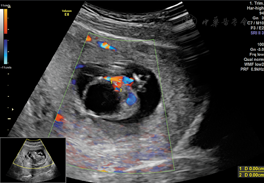

孕妇26岁,孕1产0,孕12+5周,以外院诊断腹部囊实性包块来我院进一步检查。患者及其配偶体健,无其他病史及不良习惯,家族中无类似患者,患者否认直系三代有遗传病史及遗传倾向疾病。二维超声检查:胎儿颅骨光环完整,双侧脉络丛发育正常;胸腔内未见明显异常,心脏可测得四腔心、左右室流出道;胎儿腹部可测及大小约2.28 cm×1.9 cm的囊实性包块,向外突出,其内可见胃泡,另见一囊性无回声,大小约2.0 cm×1.8 cm,两侧可见脐动脉;胎儿下腹部囊性包块左侧测及两条平行骨性回声,可见一侧脚板;双上肢可见;胎儿肾及肾动脉显示不清;胎儿脊柱腰段弯曲,骶尾部测及一囊性无回声区,直径约0.36 cm(图1,图2,图3)。超声提示:胎儿先天性多发复杂畸形;胎儿人鱼序列综合征;胎儿腹部囊实性包块(腹裂不能除外);胎儿巨膀胱;胎儿脊柱裂伴侧弯。引产标本:胎儿头面部未见明显异常,双上肢可见,胸腔正常,腹腔内器官外翻、巨大膀胱,胎儿双下肢融合,可及双侧骨性结构,双足可见。与超声检查结果相符,遂行胎儿染色体检查,核型正常。